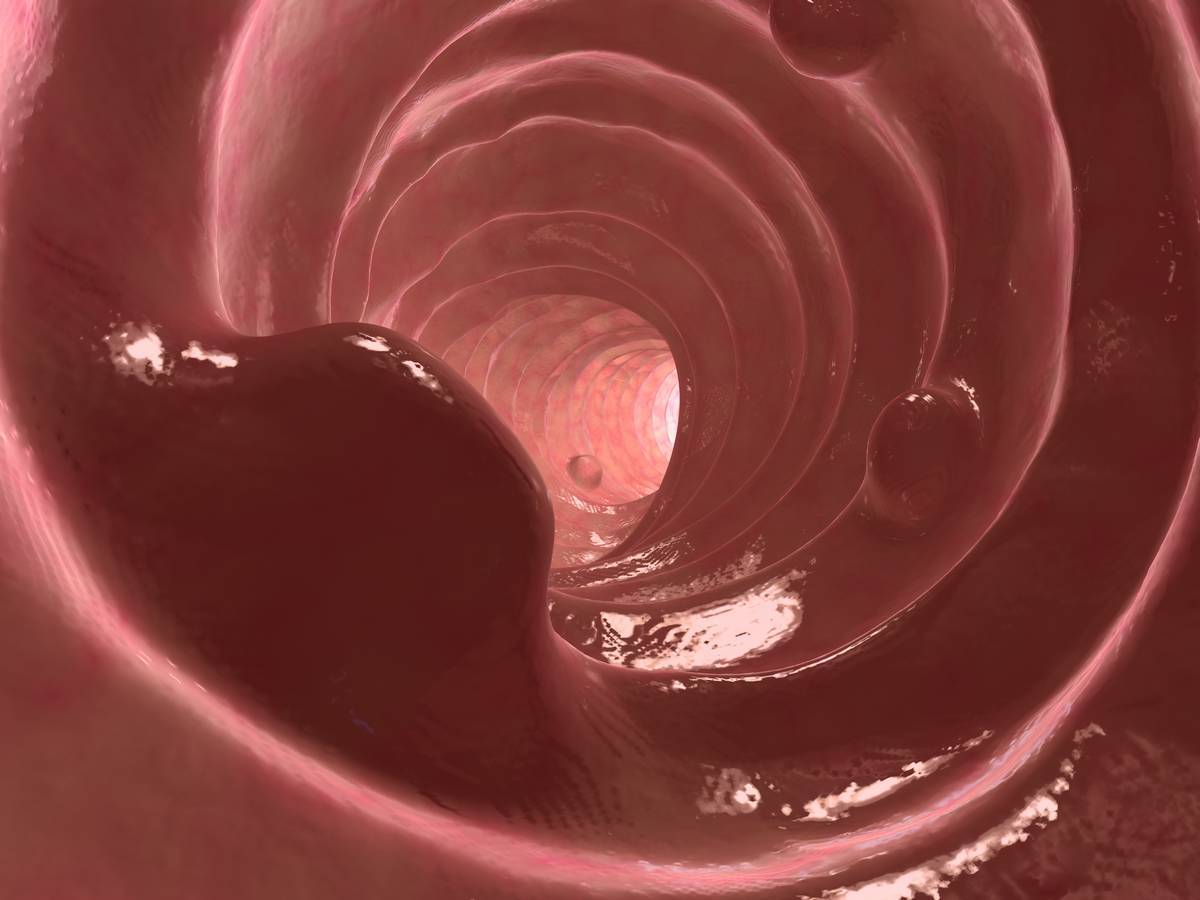

Les polypes colorectaux sont des tumeurs bénignes du côlon et du rectum, formées aux dépens de leur paroi interne. Certains de ces polypes sont susceptibles d’évoluer en tumeur cancéreuse. C’est pourquoi leur diagnostic, leur surveillance et leur traitement sont indispensables. En outre, une récente étude a montré que si vos parents proches ont eu des polypes, votre risque de souffrir d'un cancer colorectal est 40 % plus élevé.

Un polype est une tumeur bénigne pédiculée (reliée à l'organisme par un cordon contenant des vaisseaux sanguins), développée aux dépens de la muqueuse interne du côlon ou du rectum. Elle peut mesurer quelques millimètres à quelques centimètres. Les polypes peuvent être isolés, ou multiples, parfois en grappes.